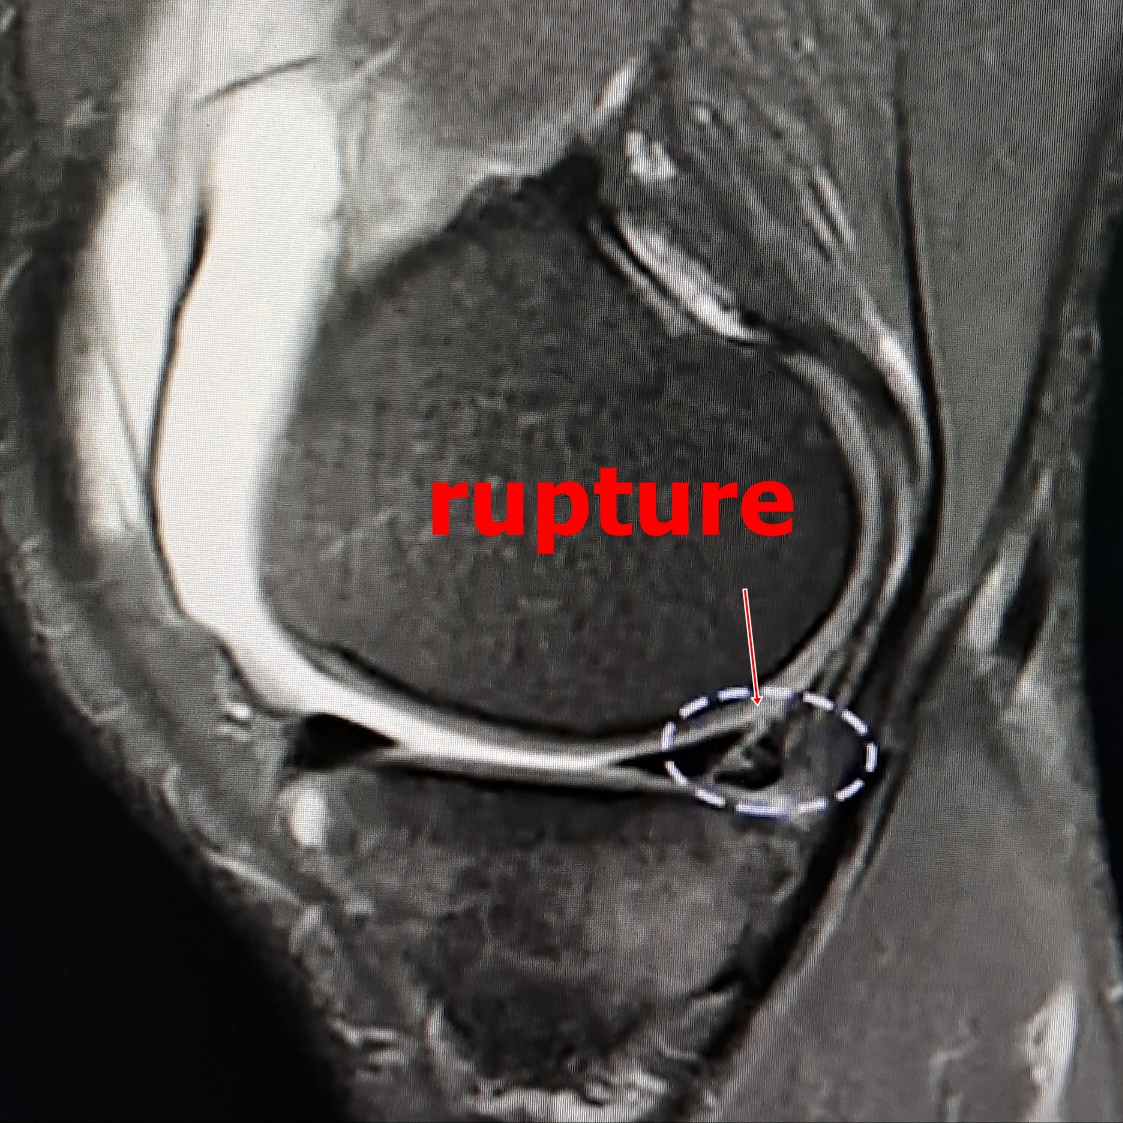

진단은 x-ray와 MRI를 찍어 손상을 확인합니다.

전방십자인대가 완전히 파열되었다면 관절경을 이용한 전방십자인대 재건술이 필요할 수 있습니다. . 이는 환자의 힘줄(슬개건, 햄스트링건 등)을 이용하여 새로운 인대를 만드는 방식입니다.

십자인대가 완전히 파열되고 불안정성이 심한 경우 퇴행성 관절염 등 여러 질환을 야기합니다. 완전히 파열된 십자인대는 저절로 붙는 자연 치유가 되지 않습니다. 십자인대 재건수술은 무릎의 안정성을 유지하기 위한 치료법으로 관절내시경을 이용하여 관절을 개방하지 않고 작은 절개를 통해 새로운 인대를 부착하여 치료율이 높고 합병증이 거의 없으며 정확한 진단과 치료가 큰 장점인 수술입니다.